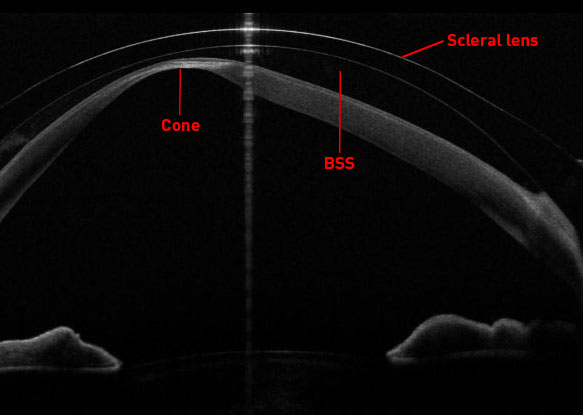

Für diejenigen, die damit nicht vertraut sind: Sklerallinsen sind eine Art von Kontaktlinsen, die die Hornhaut überbrücken und sich nur auf dem weißen Teil des Auges (der Sklera) abstützen. Die Linse ist mit steriler BSS-Lösung gefüllt, die den Raum zwischen der Hornhaut und der Linse ausfüllt. Dies macht Sklerallinsen besonders vorteilhaft für Menschen mit unregelmäßiger Hornhaut, wie z. B. unsere Patientin mit Keratokonus. Die vielen kleinen Unregelmäßigkeiten auf der Hornhautoberfläche, die zu visuellen Störungen und Aberrationen höherer Ordnung führen, werden durch die Flüssigkeit geebnet. Als Nebeneffekt kann dies auch stark trockene Augen verbessern. Am ELZA Institut haben wir unseren leitenden Optometristen, Léonard Kollros, ein sehr erfahrener, fachkundiger Skleralinsenanpasser, und der Fall, über den wir hier berichten, ist einer von ihm.